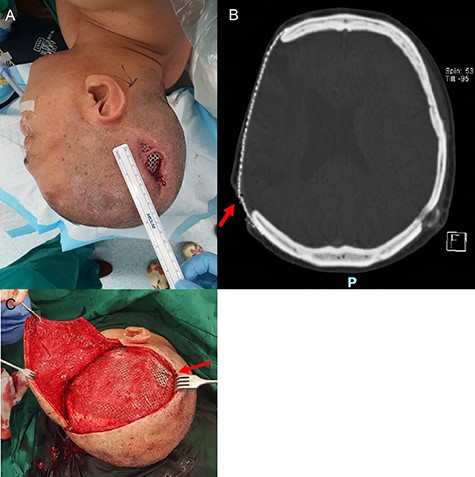

Intra-operative findings of hair-bearing skin beneath the exposed implant. The wound was debrided and incision extended along the previous scar (A). Upon removal of the implant, we found a layer of epithelium with hair follicles and surrounding granulation tissue beneath the area of the exposed implant (B, C); this was fully excised down to the dural covering layer and sent for histopathology.

Intraoperatively, venting cuts in the mesh were noted (Fig. 1C), which had likely caused pressure on the overlying skin, resulting in breakdown and implant exposure. Most interestingly, there was a layer of epithelium with hair follicles and surrounding granulation directly beneath the area of an exposed implant (Fig. 2). This was excised and sent for histopathology, which revealed dermal appendages including pilosebaceous units and eccrine glands, associated with prominent chronic inflammation (Fig. 3).

From our institutional experience, we have managed patients with exposed titanium implants who did not undergo surgery, due to significant comorbidities which increase anaesthetic risks. Surprisingly, these patients continue to survive for years without infection. Parallels can be drawn with similar situations such as osseointegrated dental implants and tissue expanders with external ports, where foreign bodies are exposed to the external environment in a stable state with minimal risk of infection [7, 8]. We hypothesise that the layer of full-thickness skin beneath the exposed implant, as shown in our patient and histopathology, could be protective. Intraoperatively, there is macroscopic evidence of granulation tissue with islands of hair-bearing skin directly beneath the exposed implant (Fig. 2). Histopathology confirmed microscopic features of full-thickness skin, with dermal appendages including pilosebaceous units and eccrine sweat glands, and even subcutaneous fat (Fig. 3). This growth of skin has likely integrated into the dural covering as would a skin graft and acts as a protective barrier against infection. A review of the literature did not reveal any published reports of such a phenomenon. We propose for this phenomenon to be called ‘dermointegration’.